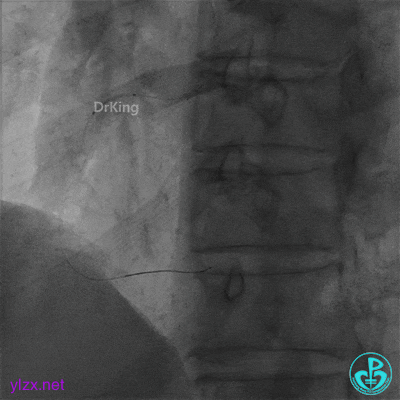

支架近端植入3.5×13mm支架覆盖夹层。

最后结果示右冠脉近端支架外仍然可见夹层。